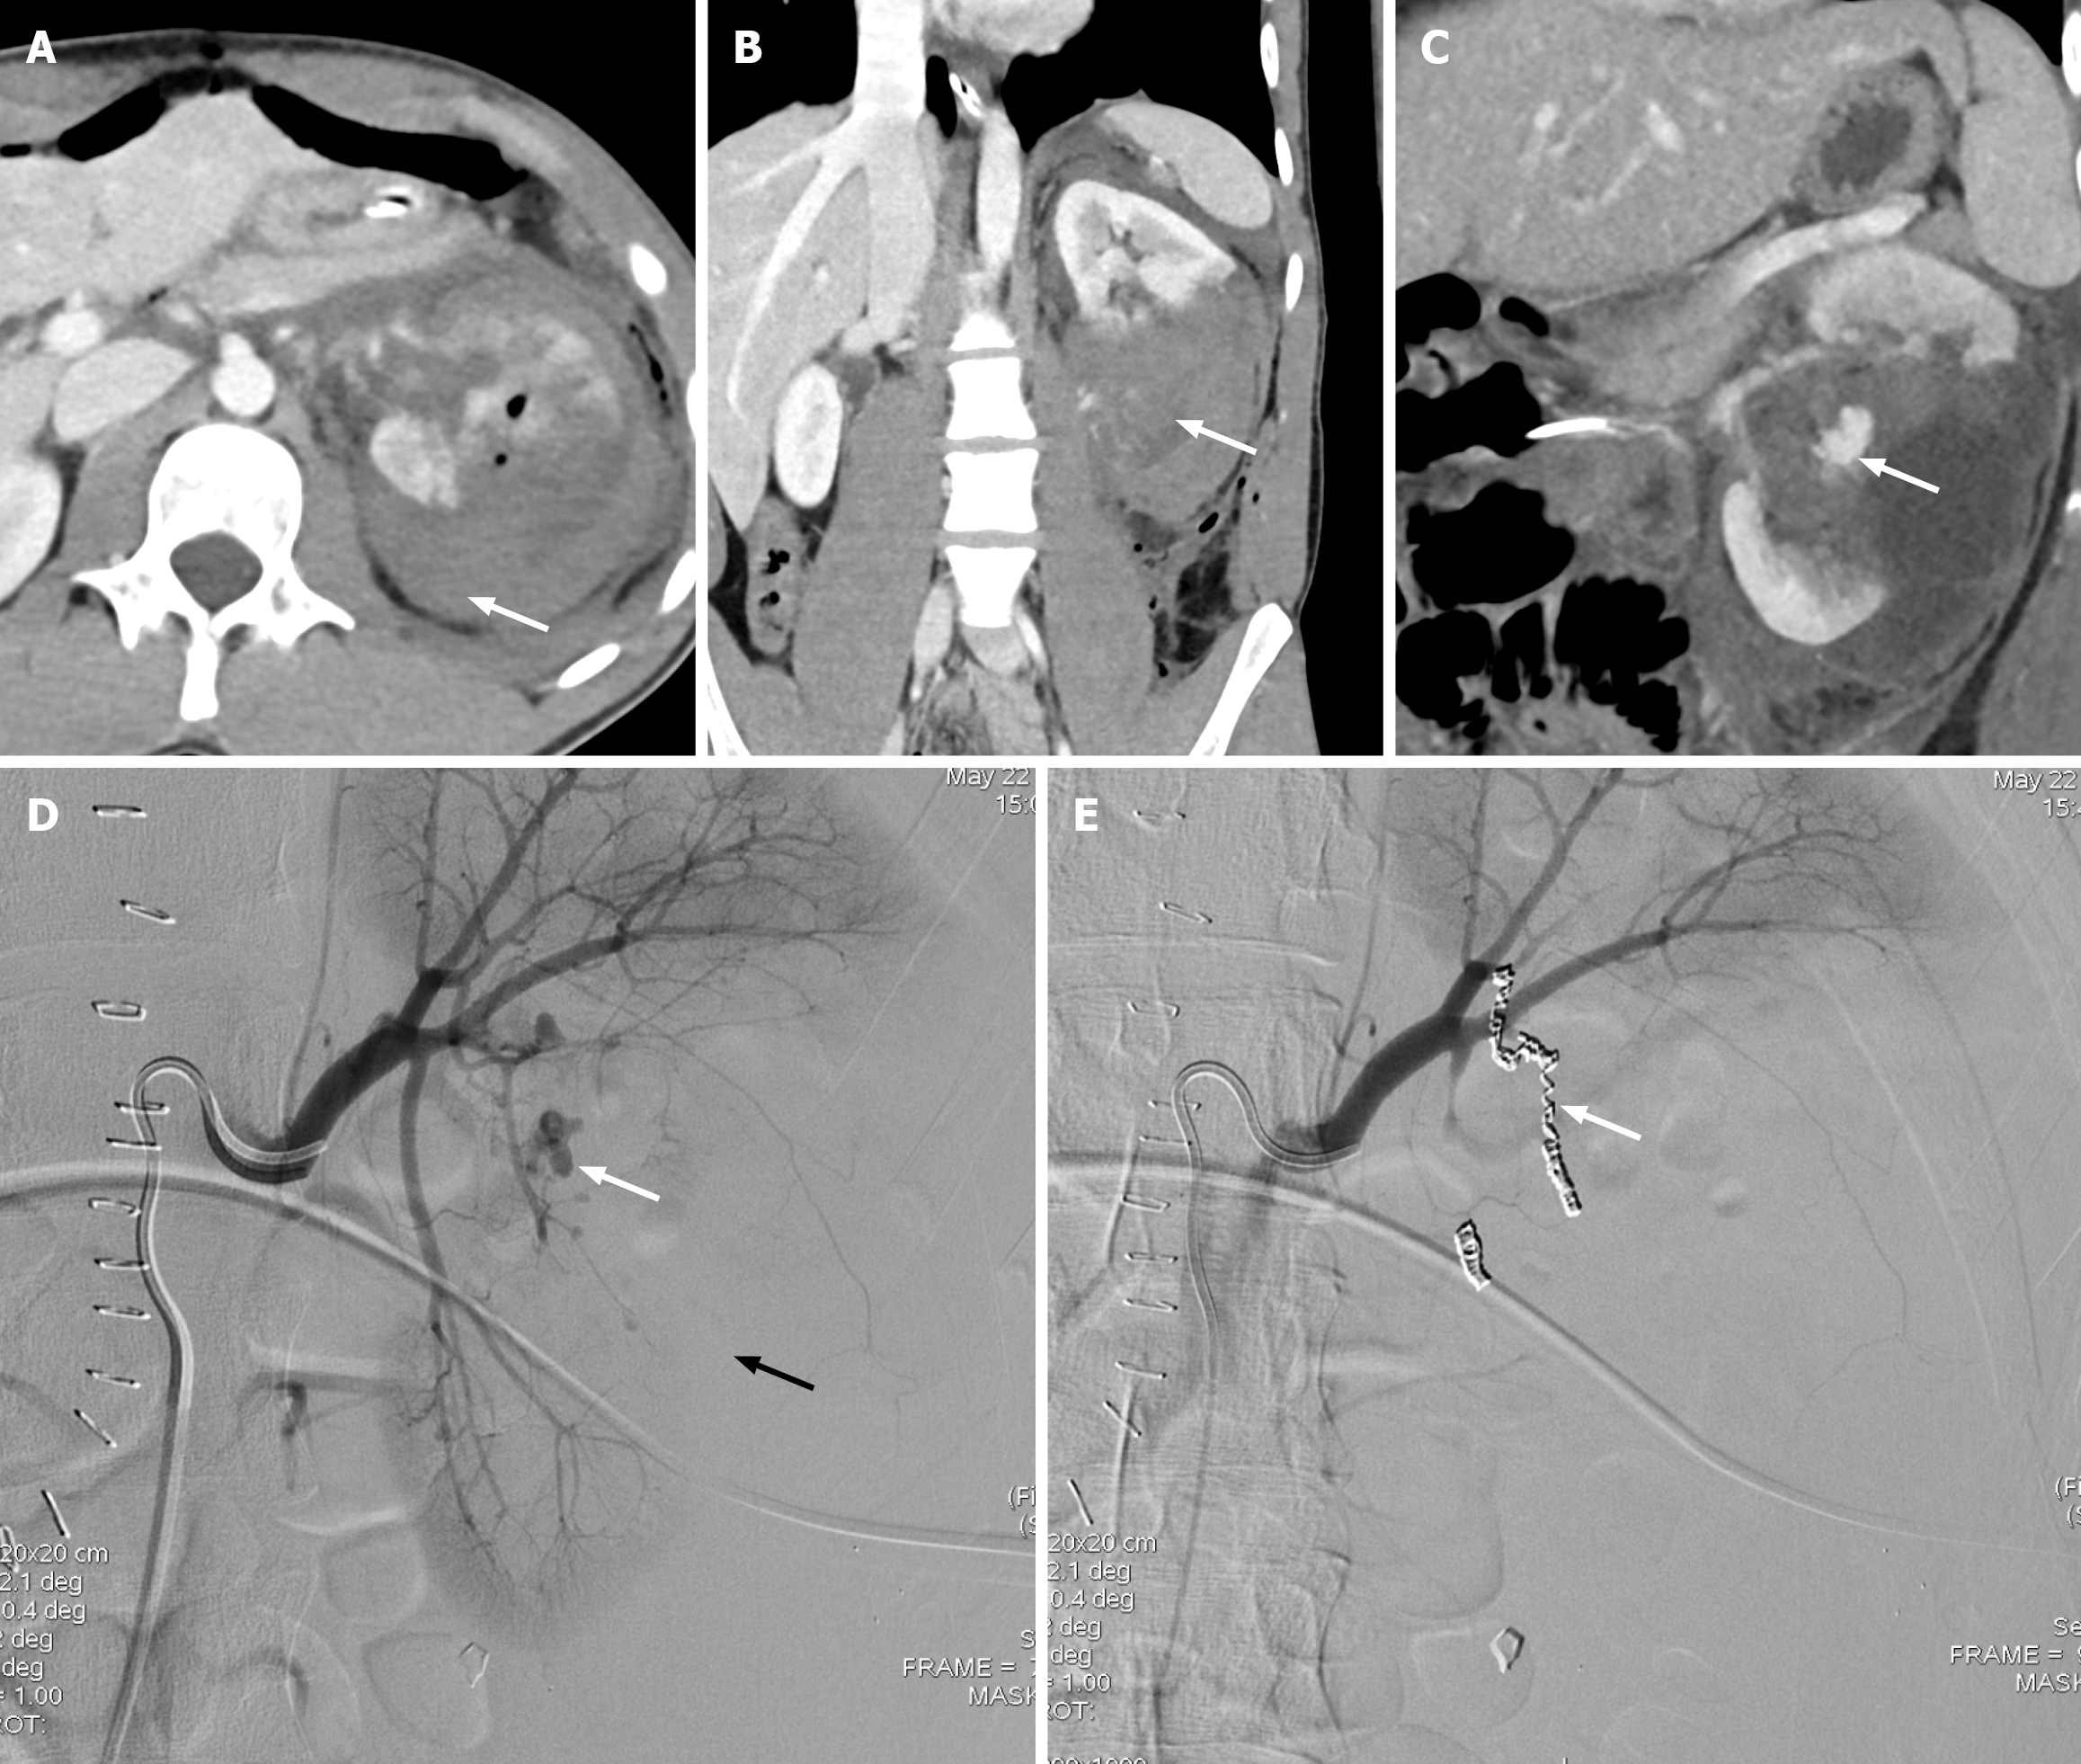

Figure 6 Grade V renal injury.

A: Axial computed tomography (CT) of the abdomen shows a shattered left kidney with foci of air and a large perinephric hematoma (white arrow); B: Coronal CT shows devascularization of the interpolar and inferior pole of the left kidney (white arrow); C: Coronal CT shows contrast blush concerning for active bleeding (white arrow). The patient was immediately taken to the interventional radiology suite; D: Left renal angiogram shows pseudoaneurysm arising from the segmental branch of the renal artery (white arrow). Note the absent perfusion of the interpolar and a part of the inferior pole regions of the left kidney (black arrow); E: Successful coil embolization of the actively bleeding renal artery branches (white arrow).